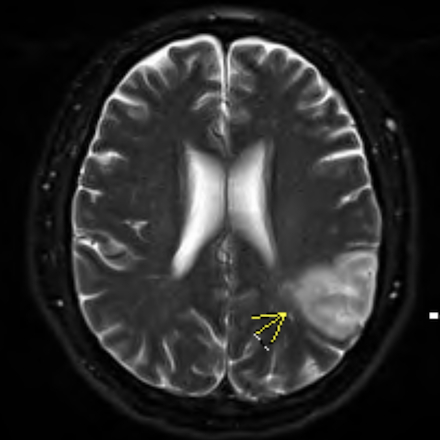

Case: A 56-year-old male with type 2 diabetes, presented with altered mental status, speech difficulty, and slurred speech. Vital signs were stable on admission. Labs showed hyperglycemia and elevated high-sensitivity troponin (peak: 3359 ng/L). EKG revealed sinus tachycardia at 109 bpm, T wave inversions in Leads 3, avF and inferior Q waves. Imaging consistent with an acute infarction in the posterior left MCA territory without hemorrhage. Transthoracic echocardiography demonstrated severely reduced ejection fraction (25–30%) with regional wall motion abnormalities and a well-defined apical thrombus.